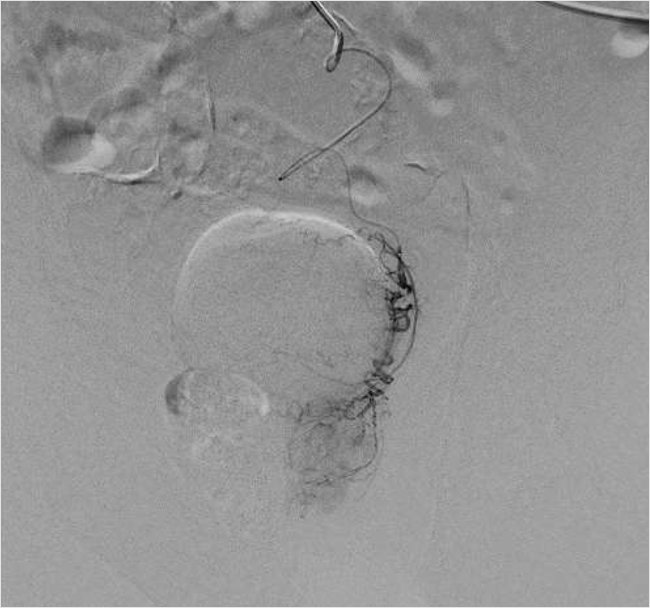

Рисунок 3. Программа syngo Embolization Guidance – цифровая программа определения и визуализации левой простатической артерии, питающей аденому простаты до эмболизации

Рисунок 5. Ангиография простатической артерии справа после эмболизации

Затем была выполнена успешная окклюзия артерий с использованием микросфер (размером 100–300 мкм) до полного стаза контраста в дистальных сегментах простатических артерий (рис. 6). Дополнительных источников кровоснабжения простаты не было выявлено. Время вмешательства составило 75 мин. Доза лучевой нагрузки при проведении вмешательства составила 871 mGy. Объем введенного контрастного препарата равнялся 150 мл.